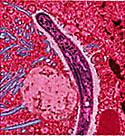

Известны 4 вида плазмодиев — возбудителей малярии человека: Plasmodium vivax — возбудитель 3-хдневной малярии; Plasmodium falciparum — возбудитель тропической малярии; Plasmodium malariae — возбудитель 4-дневной малярии и Plasmodium ovale -возбудитель овале-малярии.

image Комары рода Anopheles могут переносить малярийного плазмодия от человека к человеку. Этот процесс выглядит примерно так:

1. Инфицированного кусает не заражённый комар. В момент, когда комар пьёт кровь, в его организм попадают гаметоциты (можно сказать, половые клетки) паразита.

2. Теперь инфицированный комар кусает кого-то ещё и передаёт паразитов здоровому человеку.

3. В организме своего нового носителя, паразиты направляются к печени. Там они могут находиться несколько месяцев или даже год в спящем состоянии. В это время у заражённого может и вовсе не быть симптомов.

4. Паразиты растут и развиваются. Как только они достигают зрелости, они выходят из печени в кровоток. Именно в этот момент проявляются первые симптомы малярии.

5. Такого человека с малярией может снова укусить здоровый комар. Этот комар снова может передать малярию здоровому человеку, если укусит кого-то ещё. И цикл начинается снова.